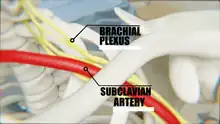

- Covering the cervicoaxillary canal, it protects the neurovascular bundle that supplies the upper limb.

Relation of Brachial Plexus with the Clavicle

Relation of Brachial Plexus with the Clavicle - Transmits physical impacts from the upper limb to the axial skeleton.